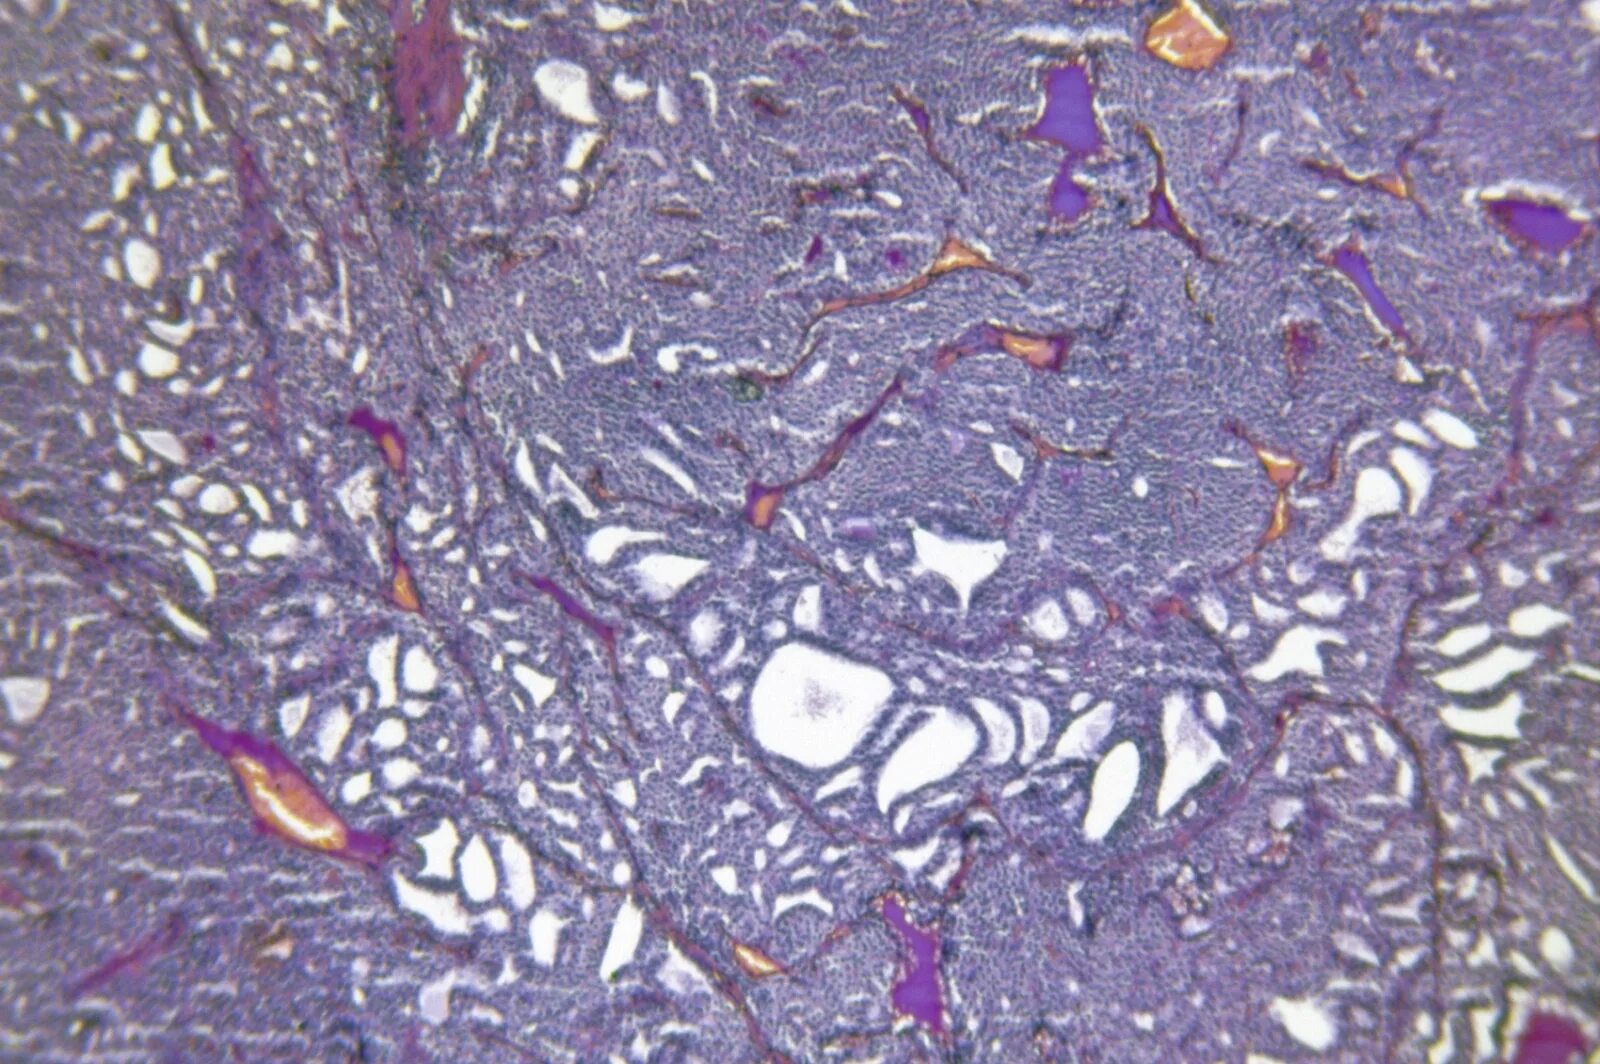

Метастазы щитовидной железы в легкие